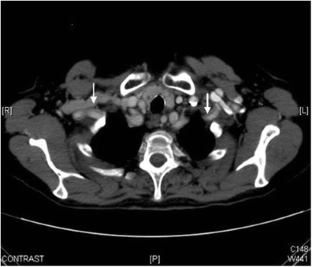

Fig. 1